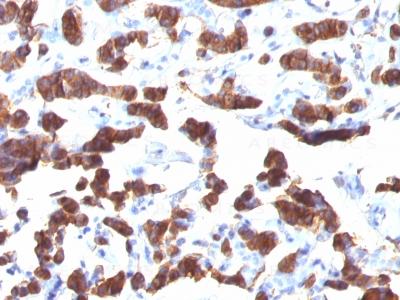

Monoclonal Antibody to Thyroglobulin (Thyroidal Cell Marker)(Clone : TGB24)

Formalin-fixed, paraffin-embedded human Thyroid Carcinoma stained with Thyroglobulin Monoclonal Antibody (TGB24).